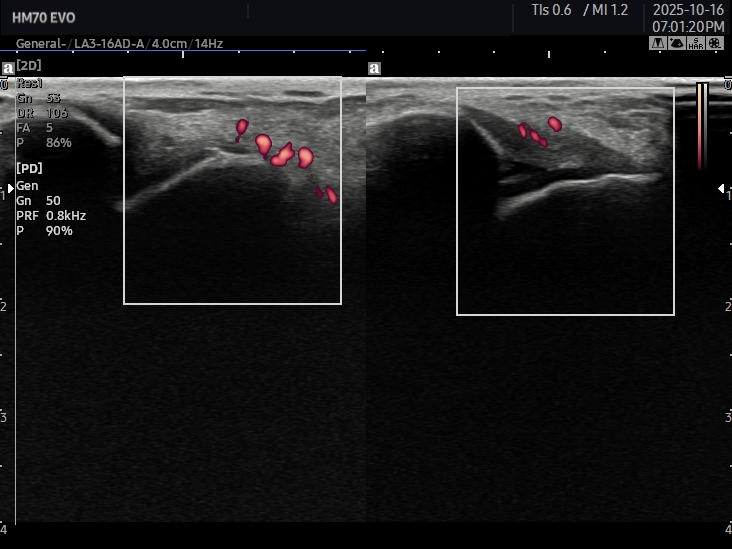

当院では

エコー(超音波)観察による評価に加え、

靱帯部の圧痛(押した時の痛み)の数を参考に重症度を判断します。